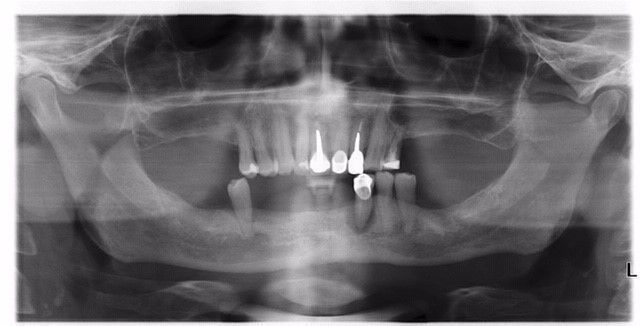

Dr. Inge De Latte beschreibt das klinische und labortechnische Vorgehen bei der Sofortversorgung eines zahnlosen Unterkiefers mit einer verschraubten zirkulären Brücke auf zwei geraden und zwei angulierten BLX Implantaten nach dem Pro-Arch Konzept. Die Implantate wurden bereits am Tag der Operation belastet, was durch deren spezifische Eigenschaften erleichtert wurde.

Bei den meisten Patienten, bei denen nach der Extraktion des Restzahnes die Vollversorgung eines Kiefers geplant ist, kann eine Unterfütterung des vorhandenen Zahnersatzes die Funktion und Ästhetik in den folgenden Wochen nicht wiederherstellen. Dieses gilt insbesondere für den Unterkiefer. Die Patienten müssen in der Regel weiche Nahrung zu sich nehmen und können vernünftig sprechen. Aus diesem Grund ist die Sofortversorgung, sofern eine ausreichende Primärstabilität erreicht werden kann, eine klinisch vielversprechende Option, die die Lebensqualität gleich vom Tag des chirurgischen Eingriffs an verbessern kann [10].